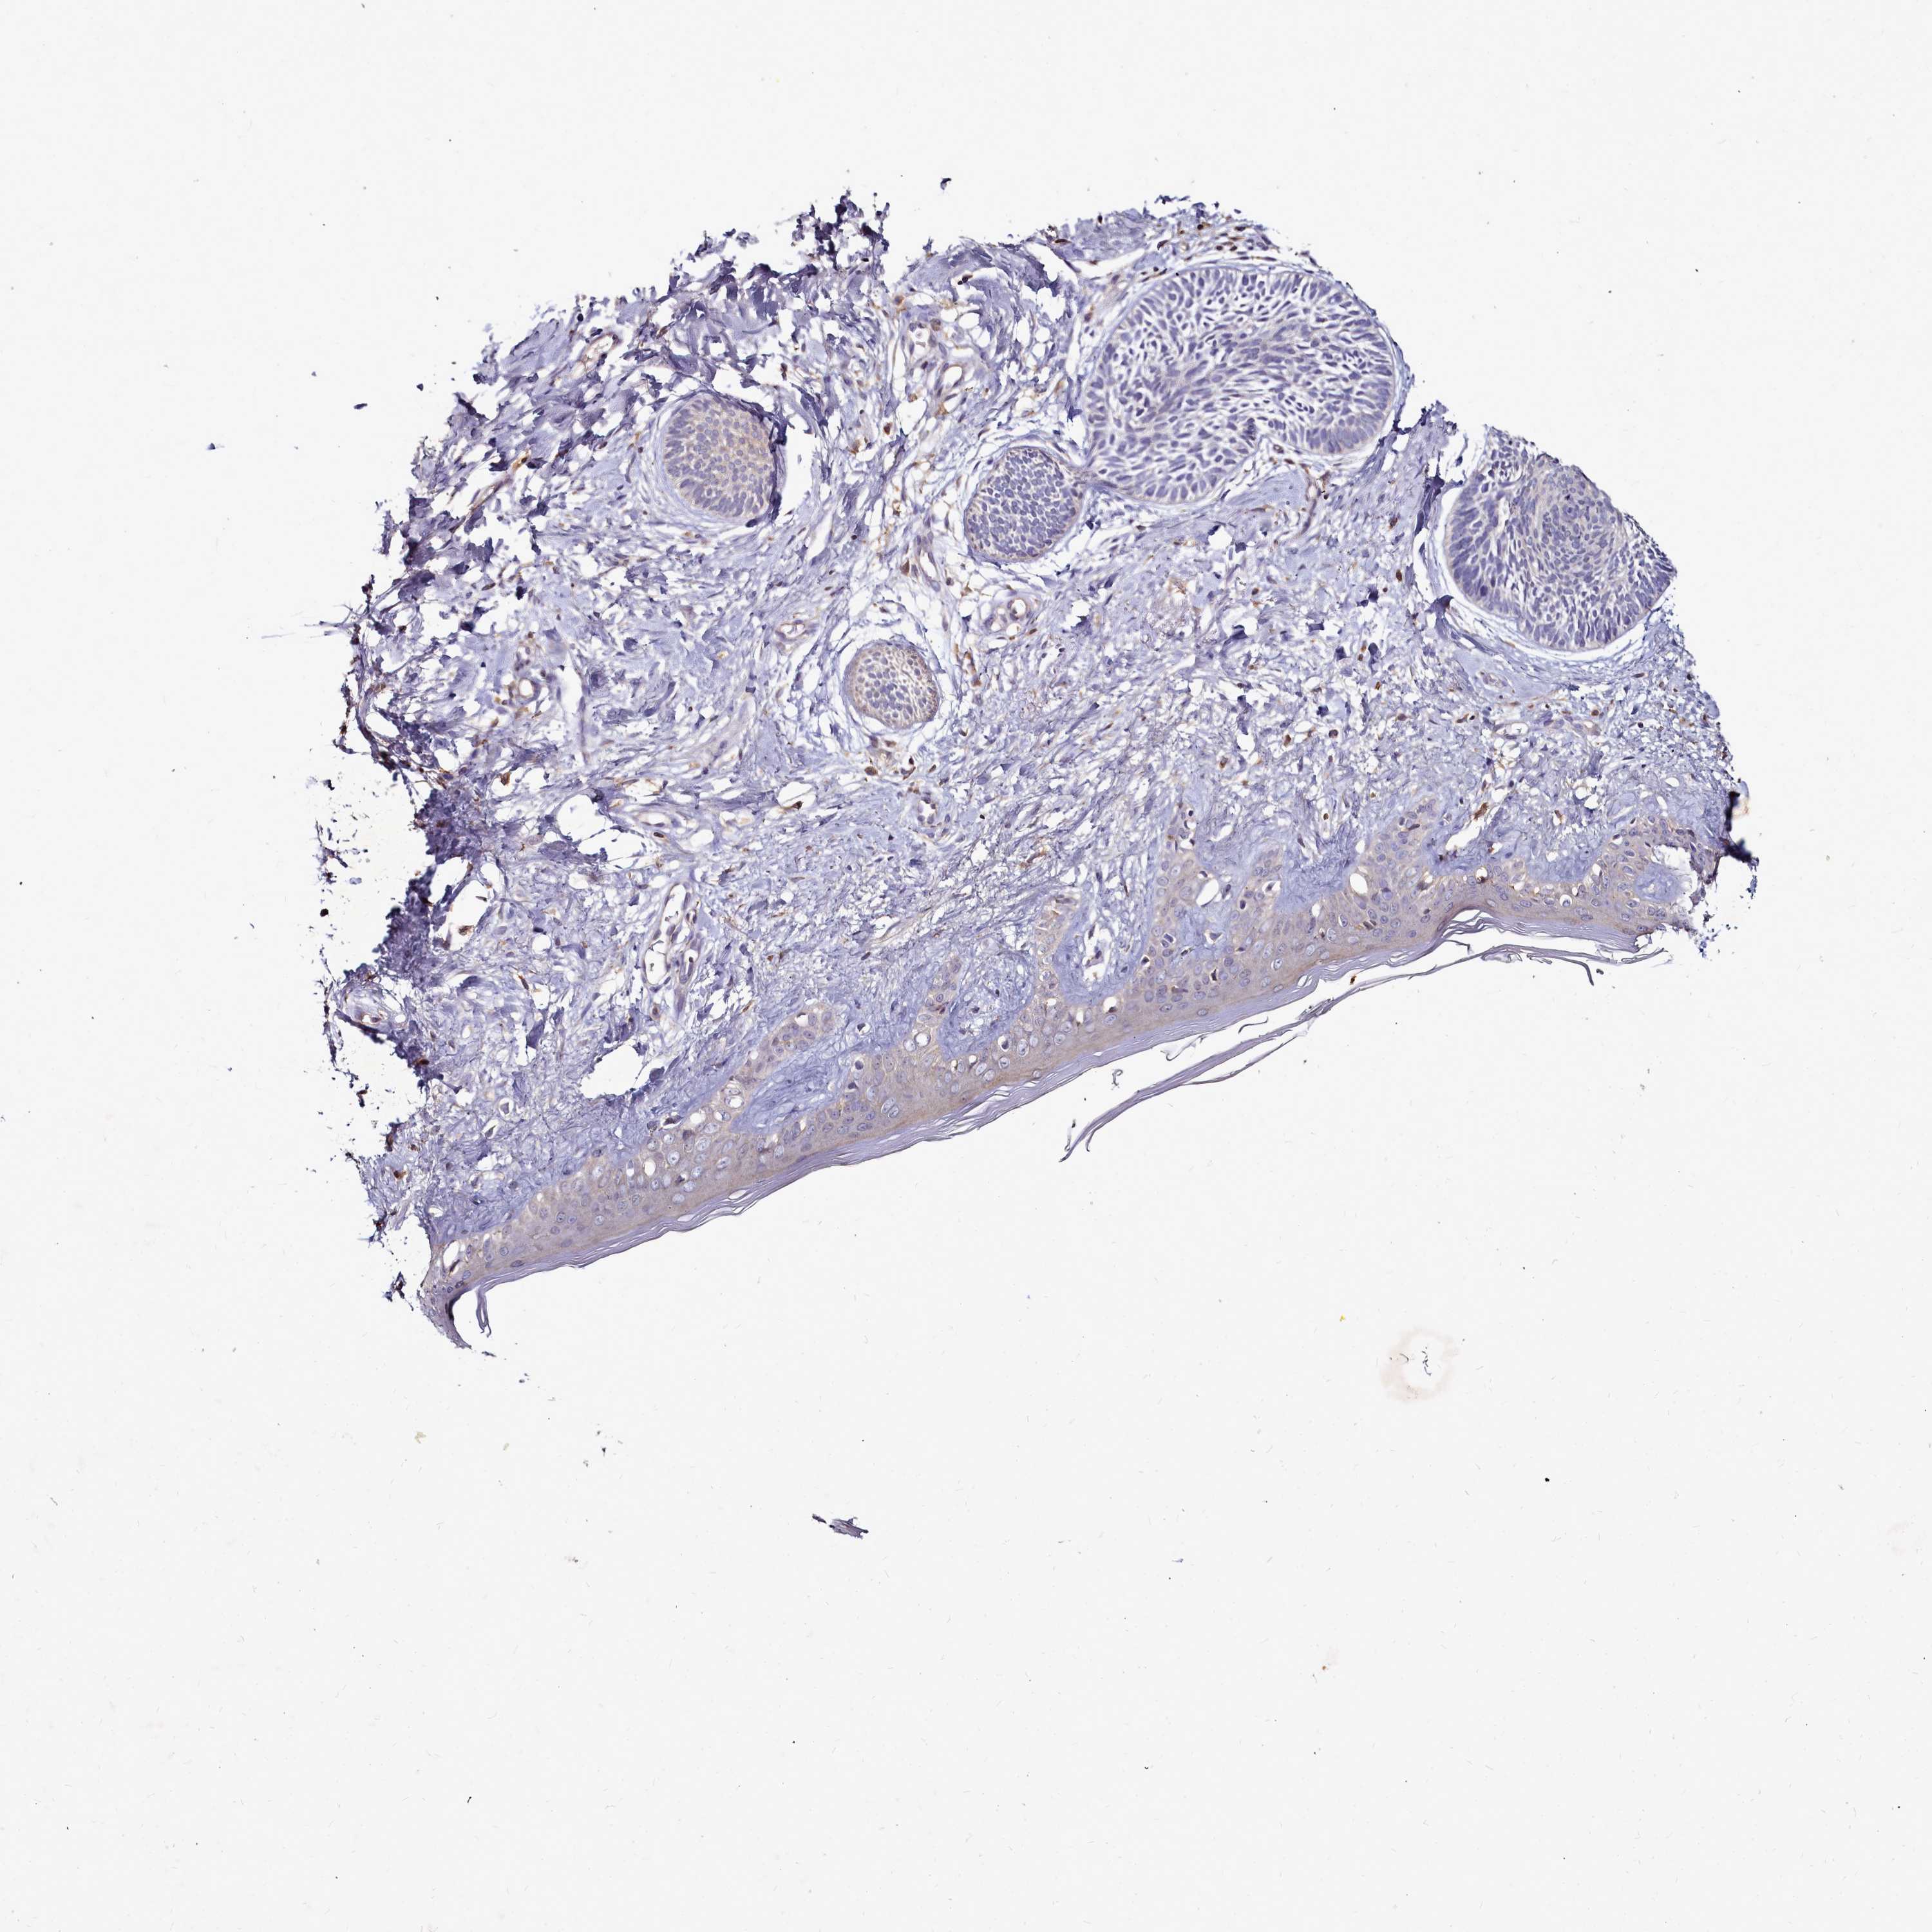

SKIN CANCER - Protein expressioni

A mouse-over function shows sample information and annotation data. Click on an image to view it in a full screen mode. Samples can be filtered based on level of antibody staining by selecting one or several of the following categories: high, medium, low and not detected. The assay and annotation is described here.

Antibody staining in the annotated cell types in the current human tissue is reported as not detected, low, medium, or high, based on conventional immunohistochemistry profiling in selected tissues. This score is based on the combination of the staining intensity and fraction of stained cells.

Each image is clickable and will lead to virtual microscopy that enables deeper exploration of all samples and also displays staining intensity scores, fraction scores and subcellular localization as well as patient and tissue information for each sample.

Antibody HPA040772

Squamous cell carcinoma, NOS